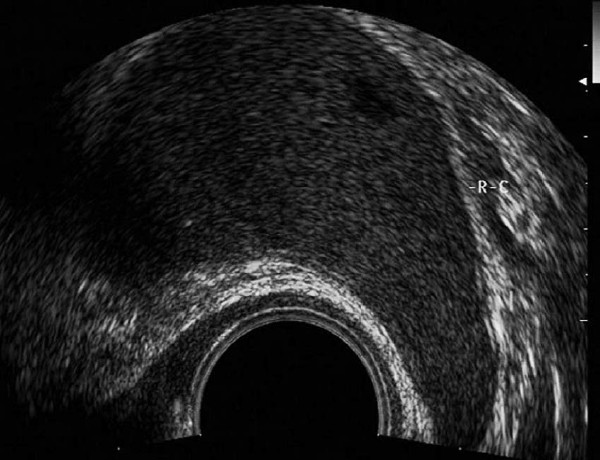

患者,女,30岁。婚后4年不孕,月经规则,曾有盆腔炎史,因下腹部坠胀、疼痛、来院诊治。超声检查报告显示:子宫后位,形态大小正常,肌壁回声均匀,内膜0.7cm,宫腔内未见明显异常。右卵巢大小4.6×2.5cm,左卵巢大小4.8×2.7cm,双附件区未见明确异常回声。盆腔内见游离液体,彩色血流未见异常。

超声提示:双侧卵巢测值偏大,盆腔积液